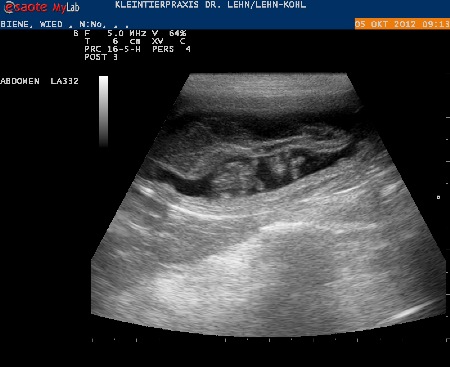

05.10.12

Wir haben uns auf den Weg zum Tierarzt gemacht - Ultraschalltermin und siehe da ...

...diese Ultraschallbilder bedürfen keiner Erläuterung ...ich denke selbst ein Laie kann gut erkennen wo die Babys sind !!!

Wieviel Welpen Biene erwartet wird wohl ihr Geheimniss bleiben bis zum Geburtstermin !!!